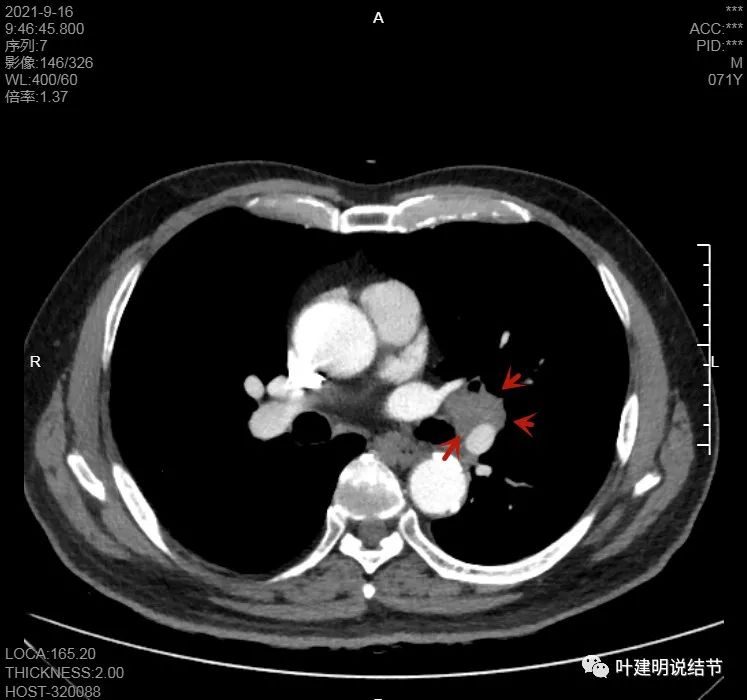

上图也示病灶是两个的,小的与大的之间有间隙的。大的病灶呈长方形似的

上图见主病灶长方形,边缘平直且光滑,没有毛刺、分叶或胸膜牵拉,粉色箭头示小病灶,在主病灶边上